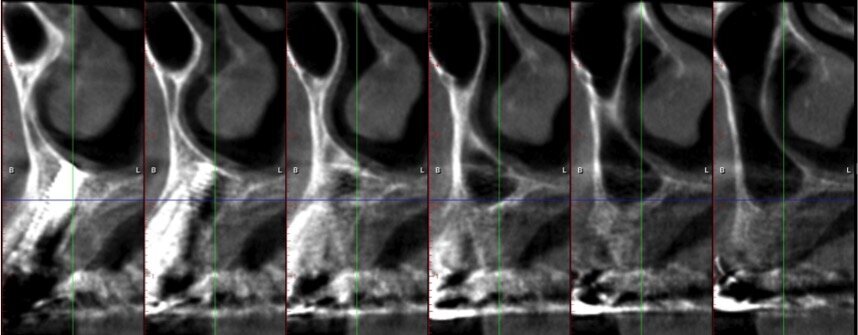

Quando le frese Densah successive avanzano nell’osteotomia, l’osso viene spinto (o densificato) verso l’estremità apicale e comincia a sollevare gradualmente la membrana di Scheneider con l’osso autologo compattato. Utilizzare sempre le frese con movimento di “pompaggio” e abbondante irrigazione, al fine di non surriscaldare l’osso. Per raggiungere una maggiore profondità verticale e il sollevamento graduale della membrana senza perforazioni si consigliano incrementi di 0,5 1,0 mm per fresa, fino ad ottenere la lunghezza e il diametro finale desiderato. Si ricorda che le frese in successione possono raggiungere un sollevamento della membrana di massimo 3 mm. Vista la scarsa qualità e quantità ossea residua del caso in questione, pur usando le frese Densah in modalità di osseodensificazione non si riesce a mantenere una integrità ossea della porzione apicale dei siti osteotomici (Fig. 5). Nei casi di incrementi superiori a 3 mm si può collocare all’interno dell’osteotomia del materiale da innesto, utilizzando l’ultima fresa con velocità di 150-200 giri/min senza irrigazione e in senso antiorario, per compattarlo all’interno dell’osteotomia. In questo caso si posizionano delle membrane di PRF all’interno dei siti osteotomici, così che la membrana di Schneider venga sollevata idrostaticamente con leggere pressioni del PRF (Fig. 6). Finita la fase di preparazione dei siti osteotomici si può procedere all’inserimento implantare a 20 giri/min e 50 Ncm di coppia (Fig. 7). Si esegue a questo punto un innesto di osso eterologo tipo “L-PRF-block”7 per incrementare il volume della zona vestibolare (Fig. 8). Sull’innesto vengono posizionate delle membrane di PRF assottigliate (Fig. 9) e una ulteriore membrana riassorbibile viene posizionata sopra il PRF per assicurare l’immobilità del tutto (Fig. 10). Si procede con l’esecuzione di scarichi di rilascio periostali, per avere un lembo privo di tensioni muscolari (Fig. 11). Infine, viene eseguita una sutura con filo 5 zeri riassorbibile monofilamento (Fig. 12). Nell’immediato post-operatorio viene eseguita alla paziente una CTCB di controllo. Come si può notare dalle sezioni della stessa, la membrana sinusale non risulta perforata, ed è sollevata sugli impianti (Figg 13, 14). Notare la neoformazione ossea apicale agli impianti a 5 mesi dall’intervento (Fig. 15).

Fig. 13 - Sezione panorex post-operatoria: si noti il sollevamento della membrana di Schneider sugli impianti.

Fig. 14 - Sezione cross section post-operatia zona 24.